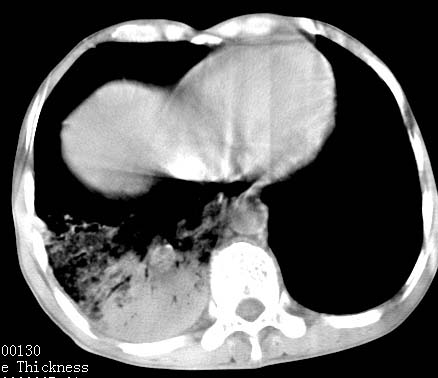

病人女 60岁 咳嗽 气促十余天,大叶性肺炎.

右肺上下叶均见 大片状密度增高影,边界清晰,其内可见支气管充气征,气管支气管通畅。纵膈略向右移位,其内无肿大淋巴结影。首先考虑炎性病变。不排除一些特异性的炎症。不知道发烧吗??wbc高吗??建议治疗后复查!!